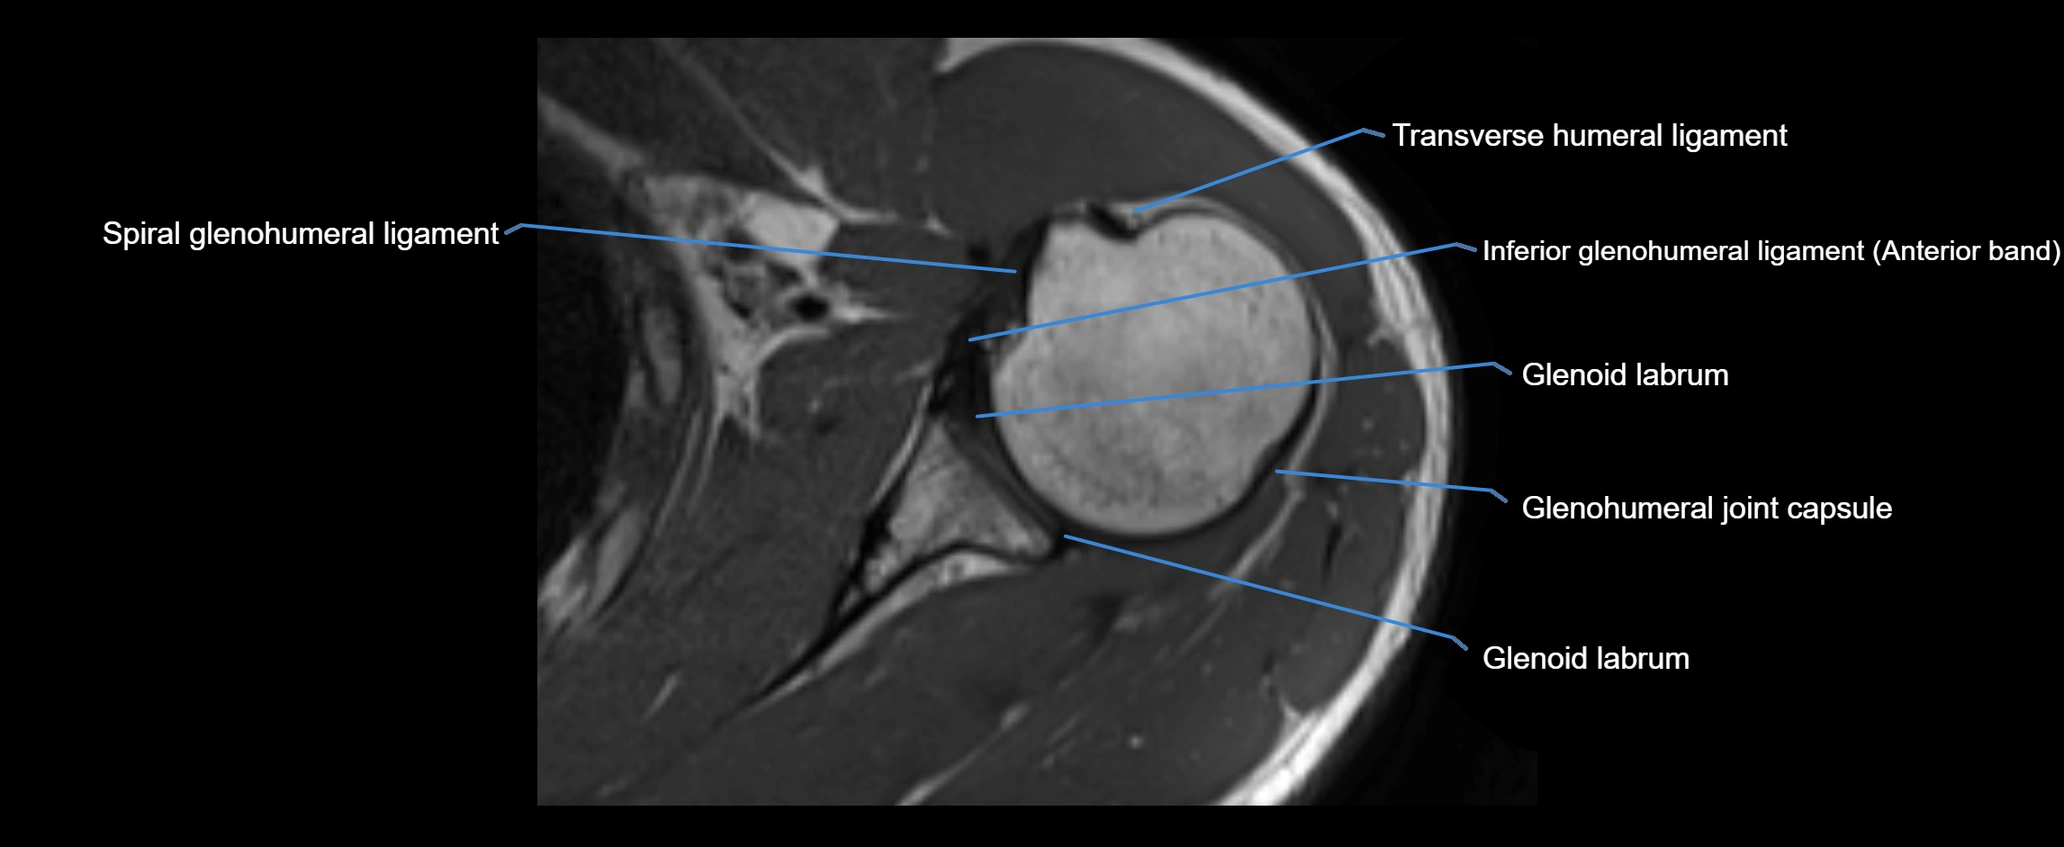

MRI images

image